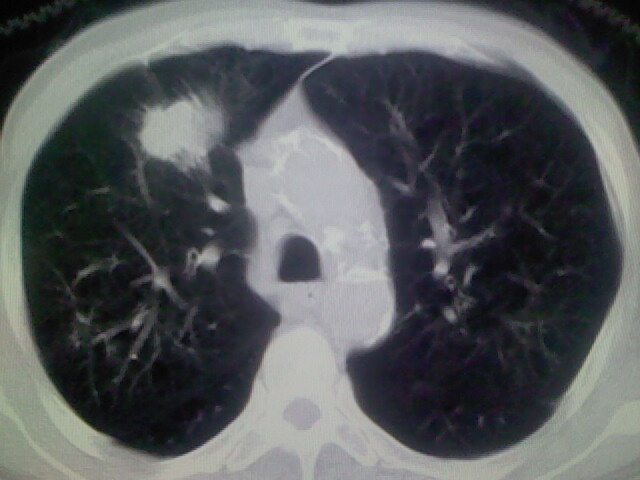

男,70y,胃占位,重度贫血,黑便3月余,伴恶心,纳差,乏力

肺内考虑原发(周围型肺癌)

右上肺周围型肺癌,肝内多发低密度影---转移瘤?建议增强;胃壁明显增厚.

右上肺周围型肺癌,肝内多发低密度影---转移瘤.

1)考虑右肺上叶周围型肺癌并纵隔及右颈部淋巴结转移,肝脏多发性转移。2)肺气肿。3)冠状动脉及主动脉钙化。

资料不清晰啊,肺内病灶内可见多发钙化影,结核不能除外.肝内符合转移瘤表现.既然楼主提供胃内占位,那原发灶还是考虑来源于胃腔.